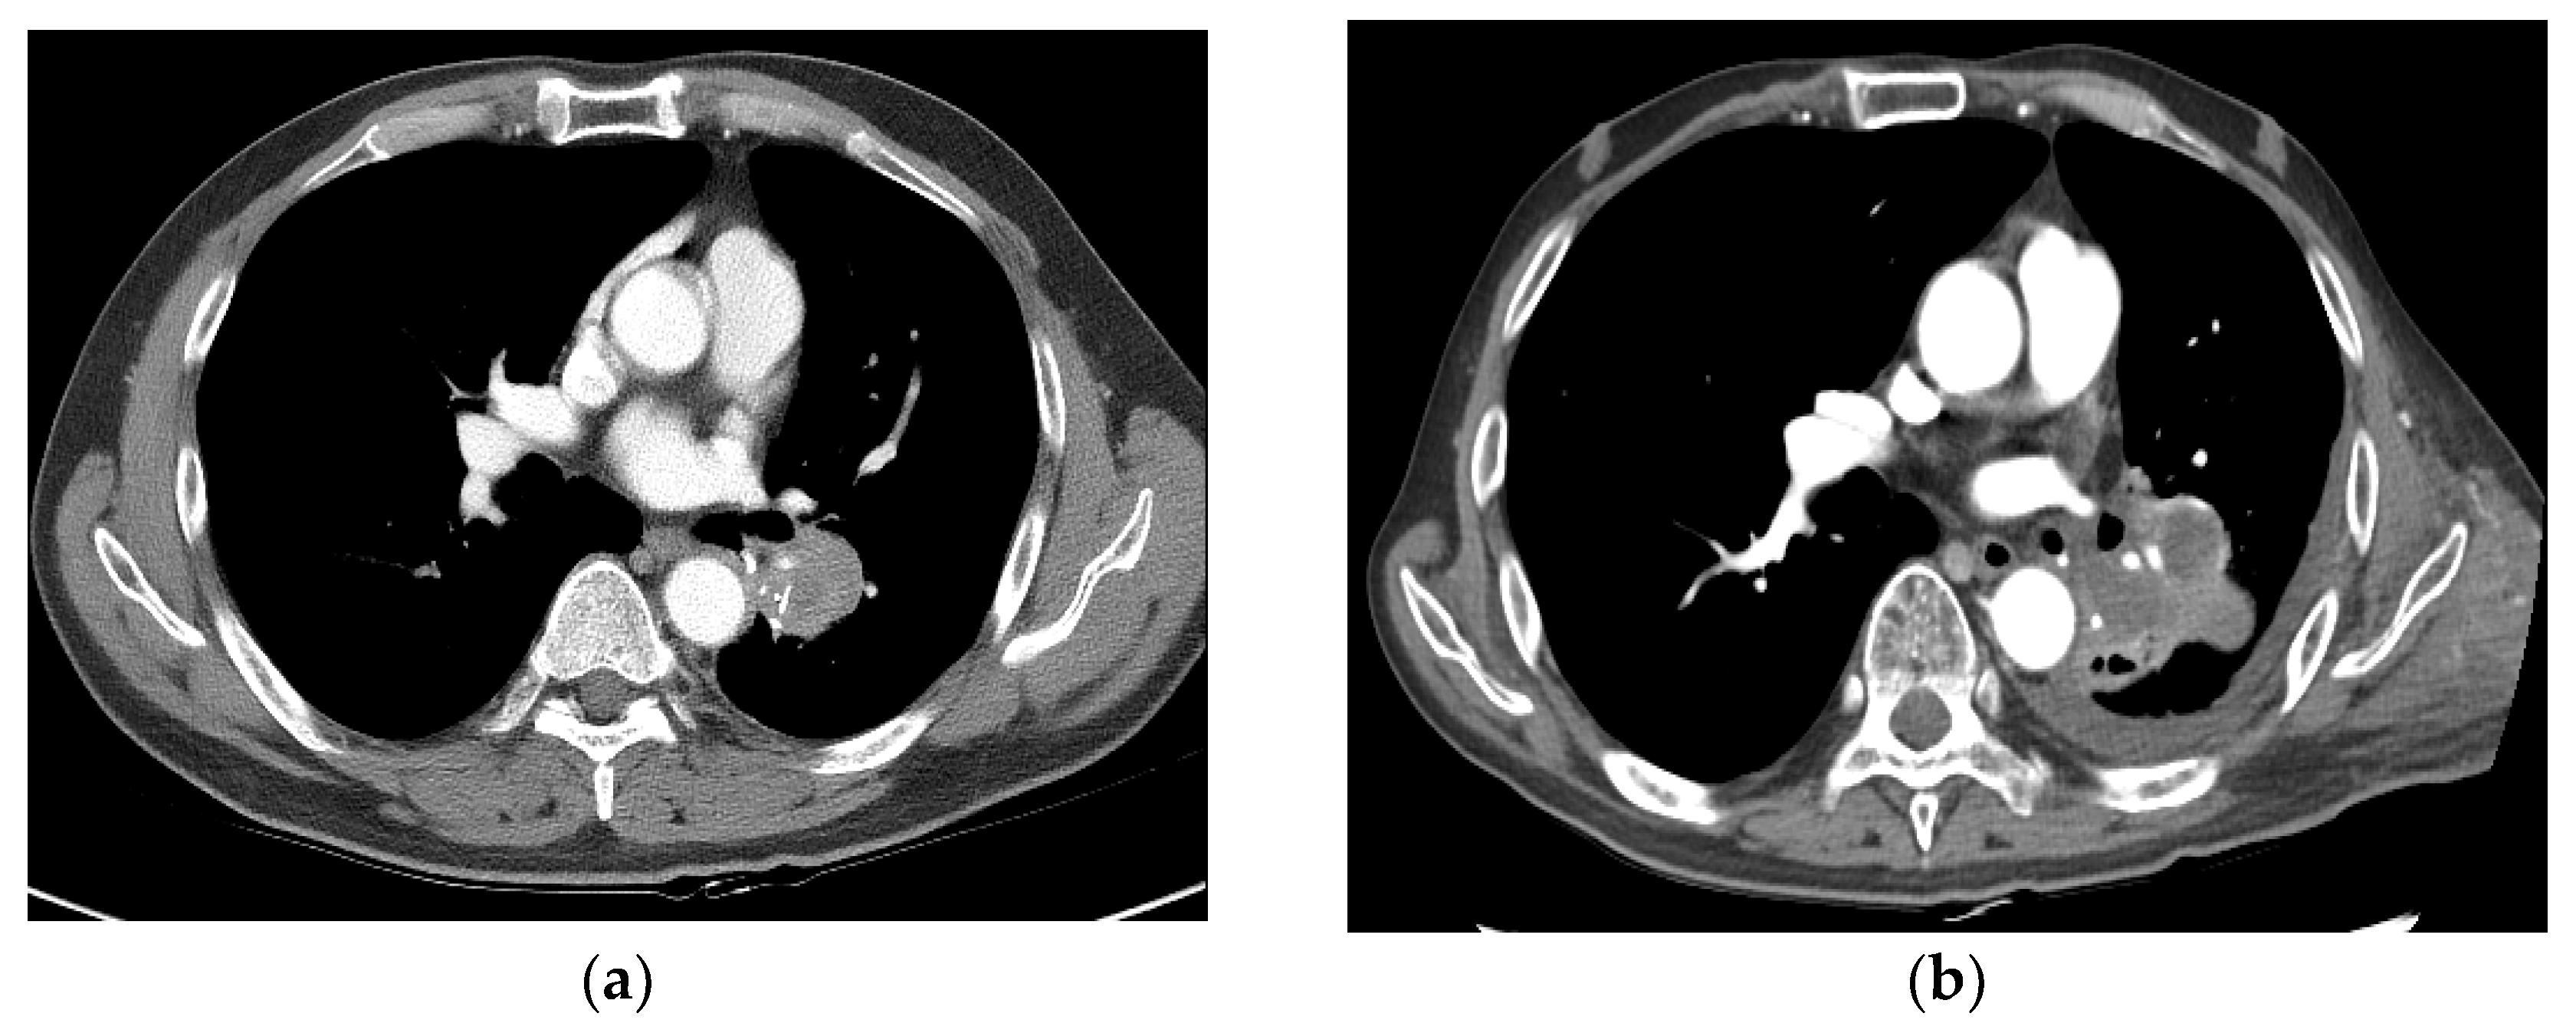

3.3. Complete Response

| 2 | 57, M | 31.3 | Primary | Tuberculosis (10 years ago) | current (30PY) | cT3N0M0 | RUL bronchus | SqCC | Rt pneumonectomy | 22.5 | 50 Gy/10 fx | CR |

| 4 | 65, M | 53.8 | Salvage s/p RULobectomy | no | never | rcT0N2 | 4R LN | ADC | Chemotherapy | 5.7 | 55 Gy/10 fx | CR |